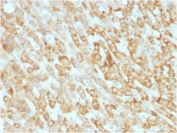

IHC testing of FFPE human hepatic carcinoma with Prohibitin antibody (clone SPM311). Required HIER: boil tissue sections in pH 9 10mM Tris with 1mM EDTA for 10-20 min followed by cooling at RT for 20 min.